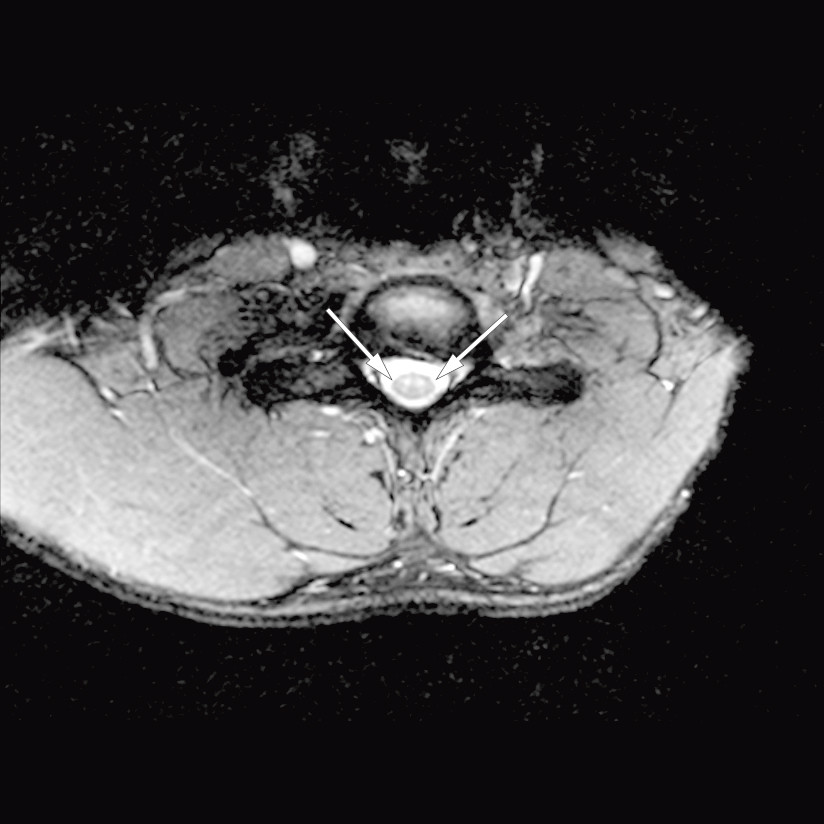

The MRI revealed increased DWI signal and reduced ADC values in the ventral part of the spinal cord from level C5 through Th1, extending almost 7 cm (Fig. 1). The spinal cord was not swollen, and no contrast enhancement was detected. An axial image (Fig. 2) at the same levels showed increased T2 signal in the anterior horn bilaterally, so-called snake-eye appearance, consistent with one of the known patterns of ischaemia in the area supplied by the anterior spinal artery. Findings of restricted diffusion with "vascular distribution" aroused suspicion of cytotoxic oedema due to acute ischemia. At this point there was no evidence of infection, as the patient was afebrile and had normal blood test results. Inflammation was still a possible differential diagnosis. There were no signal alterations and no evidence of infarction or other pathology in the cervical vertebral bodies, but somewhat dehydrated discs. Later the same day a CT angiogram of the aorta was performed, which did not reveal dissection, aneurisms or any other source of embolism.

Figure 2 Axial T2 image at level C6. Increased signal corresponding to the anterior horn bilaterally, but normal signal in…

Figure 2 Axial T2 image at level C6. Increased signal corresponding to the anterior horn bilaterally, but normal signal in surrounding medulla. The pattern is termed 'snake eyes', and is consistent with the area supplied by the anterior spinal artery.